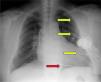

We present images from a patient who required implantation of an additional subcutaneous electrode array in the left hemithorax due to the device's failure to terminate VF during defibrillation testing, a situation that is now rarely encountered.

A 60-year-old male patient had a history of hypertension and extensive anterior myocardial infarction (MI) in 1997. Six years after the MI and following an episode of syncope, he was diagnosed with monomorphic ventricular tachycardia, with an R–R interval of 320ms. The echocardiogram revealed a dilated left ventricle with non-thickened walls, impaired global systolic function (ejection fraction of 35%), and apical dyskinesia, akinesia of the mid segments and hypokinesia of the basal segments of the anterior wall and anterior septum. Cardiac catheterization showed chronic occlusion of the proximal left anterior descending artery and 25% stenosis of the proximal circumflex. A Guidant® MINI II ICD was implanted for secondary prevention. High defibrillation thresholds were observed during ICD implantation, requiring implantation of an additional subcutaneous electrode array to enlarge the area of shock application (Figures 1–3).